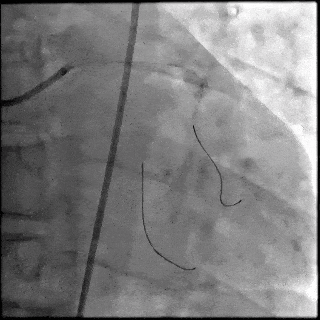

【DSA图4.治疗结束造影】

5月28日8:00,葛均波院士团队在中山医院16号楼16楼中伟厅成功连线喀什二院导管室,沪喀远程手术正式开始。8:35,新疆喀什二院导管室内股动脉入路通路建立后,行左右冠脉造影示左前降支中段存在85%的严重狭窄,狭窄位于血管分叉路口且紧邻心肌桥;且左回旋支中段近乎闭塞,血管细窄且迂曲,病变弥漫。8:59,葛院士于上海操控血管介入机器人主端PANVIS COF,将指引导管送至左冠脉开口,并操控主支导丝和分支血管保护导丝通过狭窄病变,后送至前降支和对角支血管远端以建立轨道,同时利用介入机器人的微速调整功能避开心肌桥,以亚毫米级精准定位释放1枚支架。在成功处理患者左前降支病变后,葛院士通过搓捻机械操纵杆,远程精细调整导丝“进攻”方向,顺利通过左回旋支次全闭塞病变。因血管相对细小且病变弥漫,葛院士决定采用单纯球囊扩张术处理,即刻造影提示几乎无残余狭窄,避免了额外的支架植入。10:10,撤出所有导丝及导管,手术顺利结束。